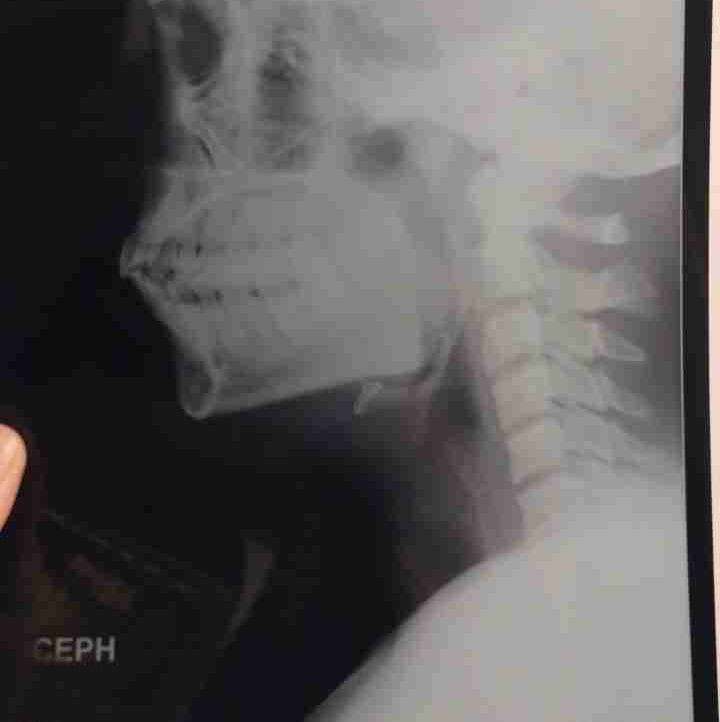

PAIN Root canal treatment is needed when dental X-rays show that the pulp has been damaged by a bacterial infection. The pulp may become inflamed if it's infected by bacteria, allowing the bacteria to multiply and spread. The symptoms of a pulp infection include: pain when eating or drinking hot or cold food and drink.

PAIN !! IN MY TOOTH .... YOU may need Root canal treatment is needed when dental X-rays show that the pulp has been damaged by a bacterial infection. The pulp may become inflamed if it's infected by bacteria, allowing the bacteria to multiply and spread.